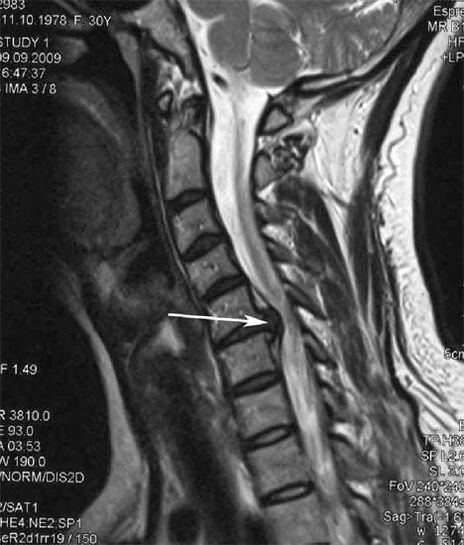

Pradinėse stadijose osteochondrozė nustatoma naudojant MRT. Vėliau patologiją galima diagnozuoti naudojant rentgenografiją. Kaklo stuburo rentgenogramose pastebimas atstumo tarp slankstelių sumažėjimas, fasetinių sąnarių patologiniai pokyčiai, osteofitozė.

Daugelis žmonių skundžiasi, kad negali pasukti kaklo dėl stipraus skausmo, atsirandančio staiga pakėlus ką nors sunkaus. Šis reiškinys rodo disko išvaržos susidarymą. Nugaros, kaklo ir viršutinės galūnės skausmo priežastis – vienos iš nugaros smegenų išeinančios nervinės šaknelės suspaudimas.

| Gimdos kaklelio osteochondrozė | Patologinių pokyčių atsiradimas viename ar keliuose stuburo judesio segmentuose. Sutrinka stuburo paslankumas, išsivysto miofascialiniai skausmo sindromai ir stuburo šaknų užspaudimas | Skausmas, parestezija ir motorikos sutrikimai gimdos kaklelio srityje, kurie plinta į pakaušį ir viršutines galūnes. Būdingų stuburo pakitimų nustatymas MRT ir rentgenogramose (osteofitai, sumažėjęs atstumas tarp slankstelių, tarpslankstelinių sąnarių pažeidimo požymiai) |